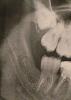

Yuls Опубликовано 18 января, 2013 Поделиться Опубликовано 18 января, 2013 Добрый день, 4 мес назад удалила сложный зуб мудрости внизу, зажило все хорошо, никаких проблем не было, ничего не беспокоит и по сей день. Сделала снимок по другому вопросу и обнаружила, что на месте удаления что-то осталось - это осколок зуба? Если да, то что теперь с этим делать и чем это опасно? Планирую беременность, поэтому хотелось бы узнать и влияние этого на беременность. Заранее большое спасибо. Ссылка на комментарий

Yuls Опубликовано 18 января, 2013 Автор Поделиться Опубликовано 18 января, 2013 (изменено) Спасибо за оперативный ответ)) А что это за "крюк" на месте зуба на втором и третьем снимке может быть? Изменено 18 января, 2013 пользователем Yuls Ссылка на комментарий

kriokov Опубликовано 18 января, 2013 Поделиться Опубликовано 18 января, 2013 Спасибо за оперативный ответ)) А что это за "крюк" на месте зуба на втором и третьем снимке может быть?зто кость челюсти , просто так выглядит на снимке. имхо Ссылка на комментарий

Yuls Опубликовано 18 января, 2013 Автор Поделиться Опубликовано 18 января, 2013 (изменено) Еще вопросик: а затемнение на месте этого злосчастного 8го зуба - это что? Изменено 18 января, 2013 пользователем Yuls Ссылка на комментарий

kriokov Опубликовано 18 января, 2013 Поделиться Опубликовано 18 января, 2013 Еще вопросик: а затемнение на месте этого злосчастного 8го зуба - это что?место в кости, где зуб ранее находился, именно так на снимке после удаления и выглядит Ссылка на комментарий

АнтонТЛТ Опубликовано 18 января, 2013 Поделиться Опубликовано 18 января, 2013 Спасибо за оперативный ответ)) А что это за "крюк" на месте зуба на втором и третьем снимке может быть?Вероятно это межкорневая перегородка Ссылка на комментарий

Yuls Опубликовано 20 января, 2013 Автор Поделиться Опубликовано 20 января, 2013 Вероятно это межкорневая перегородка а что это за перегородка - она должна была остаться? я волнуюсь, чтоб это не дало о себе знать потом, чтоб все было чисто Ссылка на комментарий

Bier Опубликовано 21 января, 2013 Поделиться Опубликовано 21 января, 2013 а что это за перегородка - она должна была остаться? я волнуюсь, чтоб это не дало о себе знать потом, чтоб все было чистоДа, это часть челюсти Ссылка на комментарий